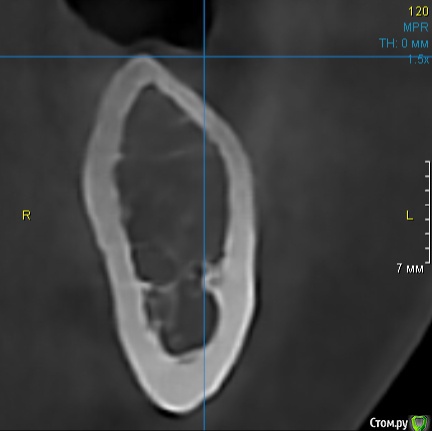

Dman Опубликовано 16 сентября, 2019 Поделиться Опубликовано 16 сентября, 2019 Девушка 30 лет, зубы были удалены в 17.На кт губка отсутствует практически в 0, какую тактику бы выбрали вы? ПС. очень неудобно что нельзя в поиск вбить "д4" - не ищет(( Ссылка на комментарий

Dman Опубликовано 18 сентября, 2019 Автор Поделиться Опубликовано 18 сентября, 2019 А другие участки кт? Все так же? да, в области отсутствующих 36, 37 вся кость такого вида Ссылка на комментарий

Astronaft Опубликовано 20 сентября, 2019 Поделиться Опубликовано 20 сентября, 2019 Это характерная картина "кавитации". Если читаете на английском: Neuralgia-inducing cavitational osteonecrosisЕсли по-простому, то это незажившая кость, скорее всего в результате ишемии. Я делал биопсию такого очага. Сравнивал с результами других докторов. Всегда похожая картина: недифференцированные клетки соединительной ткани, очаги грануляций. Если цель поставить имплант: стабилизироваться в кортикалке, ставить формик, под нагрузкой постепенно сформируются трабекулы вокруг импланта. Если заживить очаг: раскрыться, откюретажить все, добиться что бы хорошо кровило и дать 3-4 месяца. 6 Ссылка на комментарий